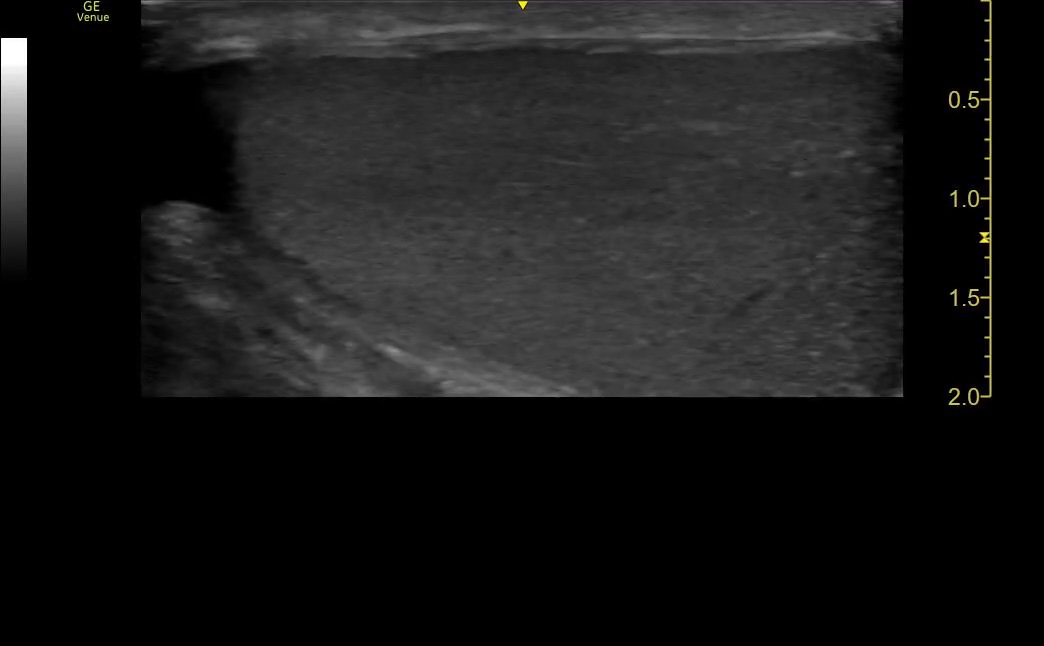

Too little depth

In general, we want to see the entire AOI on the screen – none of it should be cut off. The concern in this case is not wasted pixels on the screen but incomplete visualization of the AOI.

However, the machine does not know what the body habitus is. Nor does it know what view you are obtaining. When doing a FAST exam, you must keep in mind that the bladder is usually much more superficial than Morrison’s Pouch. The pleura is even more superficial than than the bladder. You wouldn’t expect the same setting to be ideal for all of them. It’s a dynamic exam.